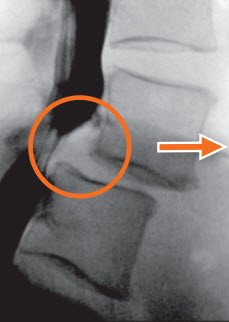

Zu eng wird der Wirbelkanal als Folge von Abnützungen oder von angeborenen Veränderungen der Lendenwirbelsäule. Die Arthrose, d. h. die Verdickung der Wirbelgelenke, zum Teil mit verschleissbedingter Wirbelverschiebung, ist aber die häufigste Ursache einer Verengung des Spinalkanals.

Die Diagnose des engen Spinalkanals im Lendenbereich wird gestellt anhand der Beschwerdenbeschreibung und der Befunde der neurologischen Untersuchung sowie der bildgebenden Diagnostik (Röntgenbilder, Computertomographie, Kernspintomographie, Myelographie). Das geeignetste Verfahren ist nicht in allen Fällen gleich und ist abhängig von der neurologischen Untersuchung.